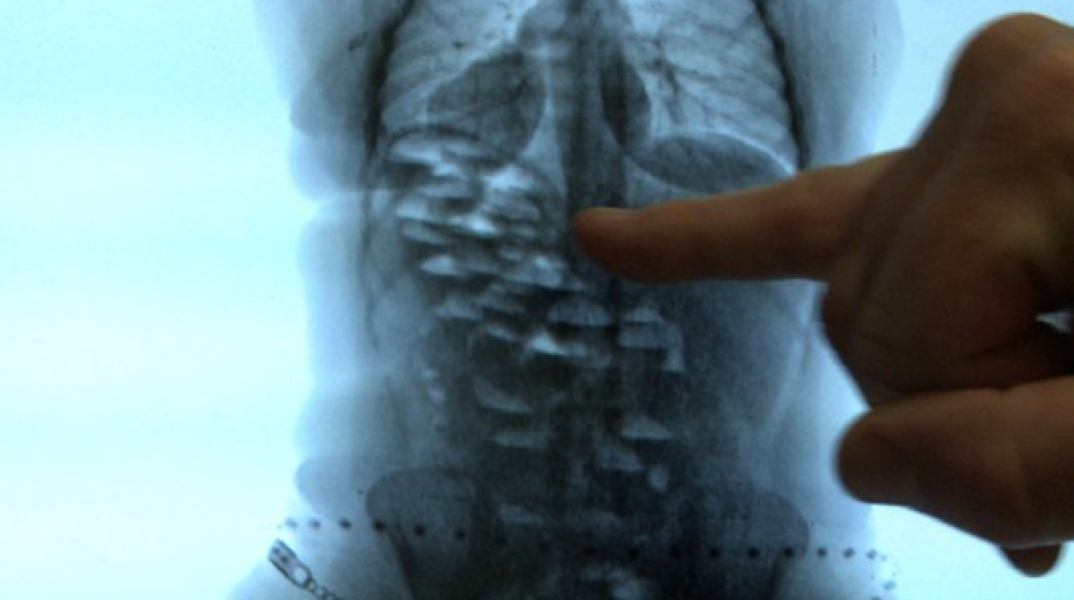

Μέσα στο στομάχι του 70 αυτοσχέδιες συσκευασίες

Σύμφωνα με την αστυνονία, ο συλληφθείς είχε καταπιεί 70 αυτοσχέδιες συσκευασίες με κοκαΐνη συνολικού βάρους 960 γραμμαρίων.